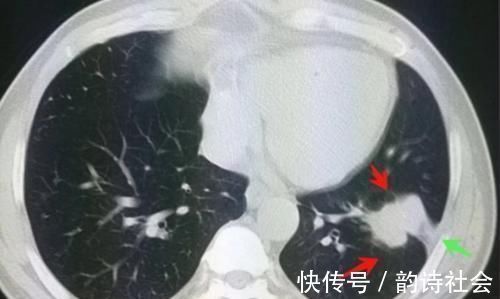

文章插图

像这位病人心太大了,反复的左侧胸背疼半年才来看,肿瘤已经侵犯胸膜,不是早期了。

如果半年前进来检查,肯定不至于长这么大!

好在他运气指数也高于常人,胸腔镜手术后做了化疗,已经快5年了,没有复发!